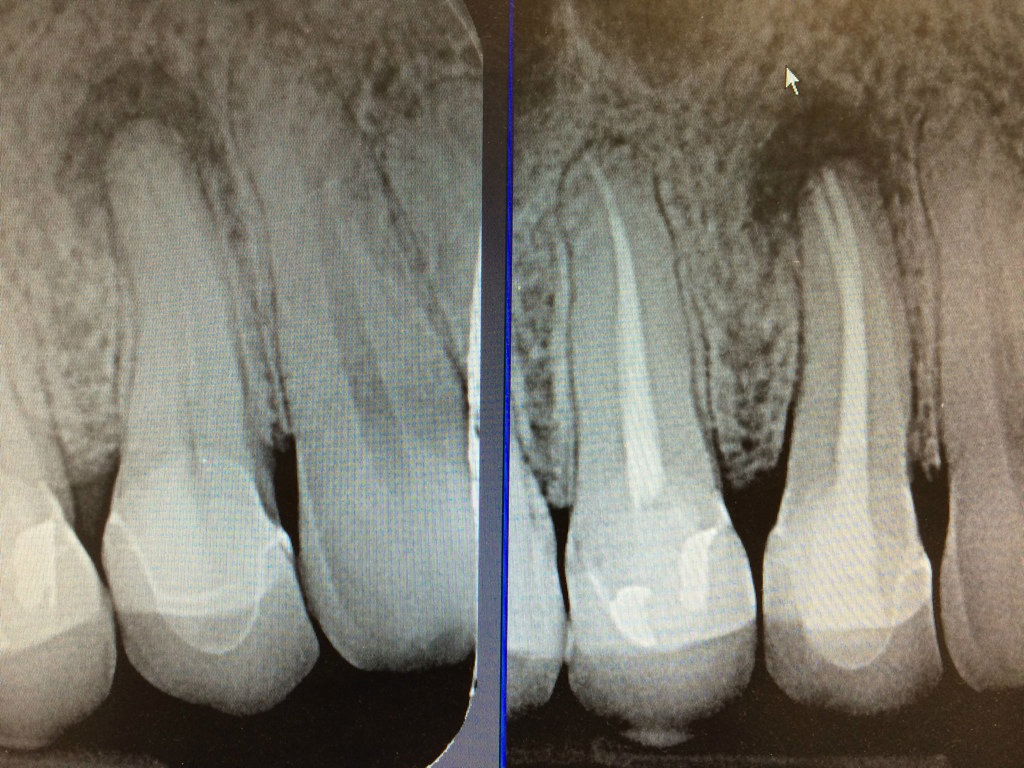

Root Canal Treatment

Root Canal Treatment is a procedure performed on the infected tooth to remove the decay affecting the pulp (underlying tissue containing blood vessels and nerve supply to a tooth). Simple filling procedure cannot restore a tooth’s dental health when the infection has encroached the pulp. Root canal therapy is the only alternative to save such tooth from being extracted. The main objective of root canal treatment is to preserve the infected existing natural tooth by disinfection. During a root canal therapy, access to the root canal present inside the root of a tooth is gained and the infected tissue is removed entirely. Hence Root Canal treatment bypasses extraction of the infected tooth and its replacement procedures thereby saving time and money.